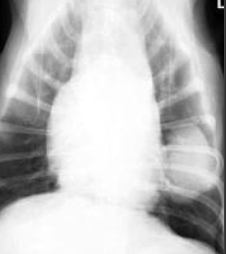

what is hypertrophic osteopathy (HO)?

periosteal proliferation of new bone along shafts of long bones associated with malignant and non-malignant diseases

how/where does hypertrophic osteopathy appear on rads?

symmetrical periosteal new bone formation, nodular or speculated

classically radiating 90degrees from long axis